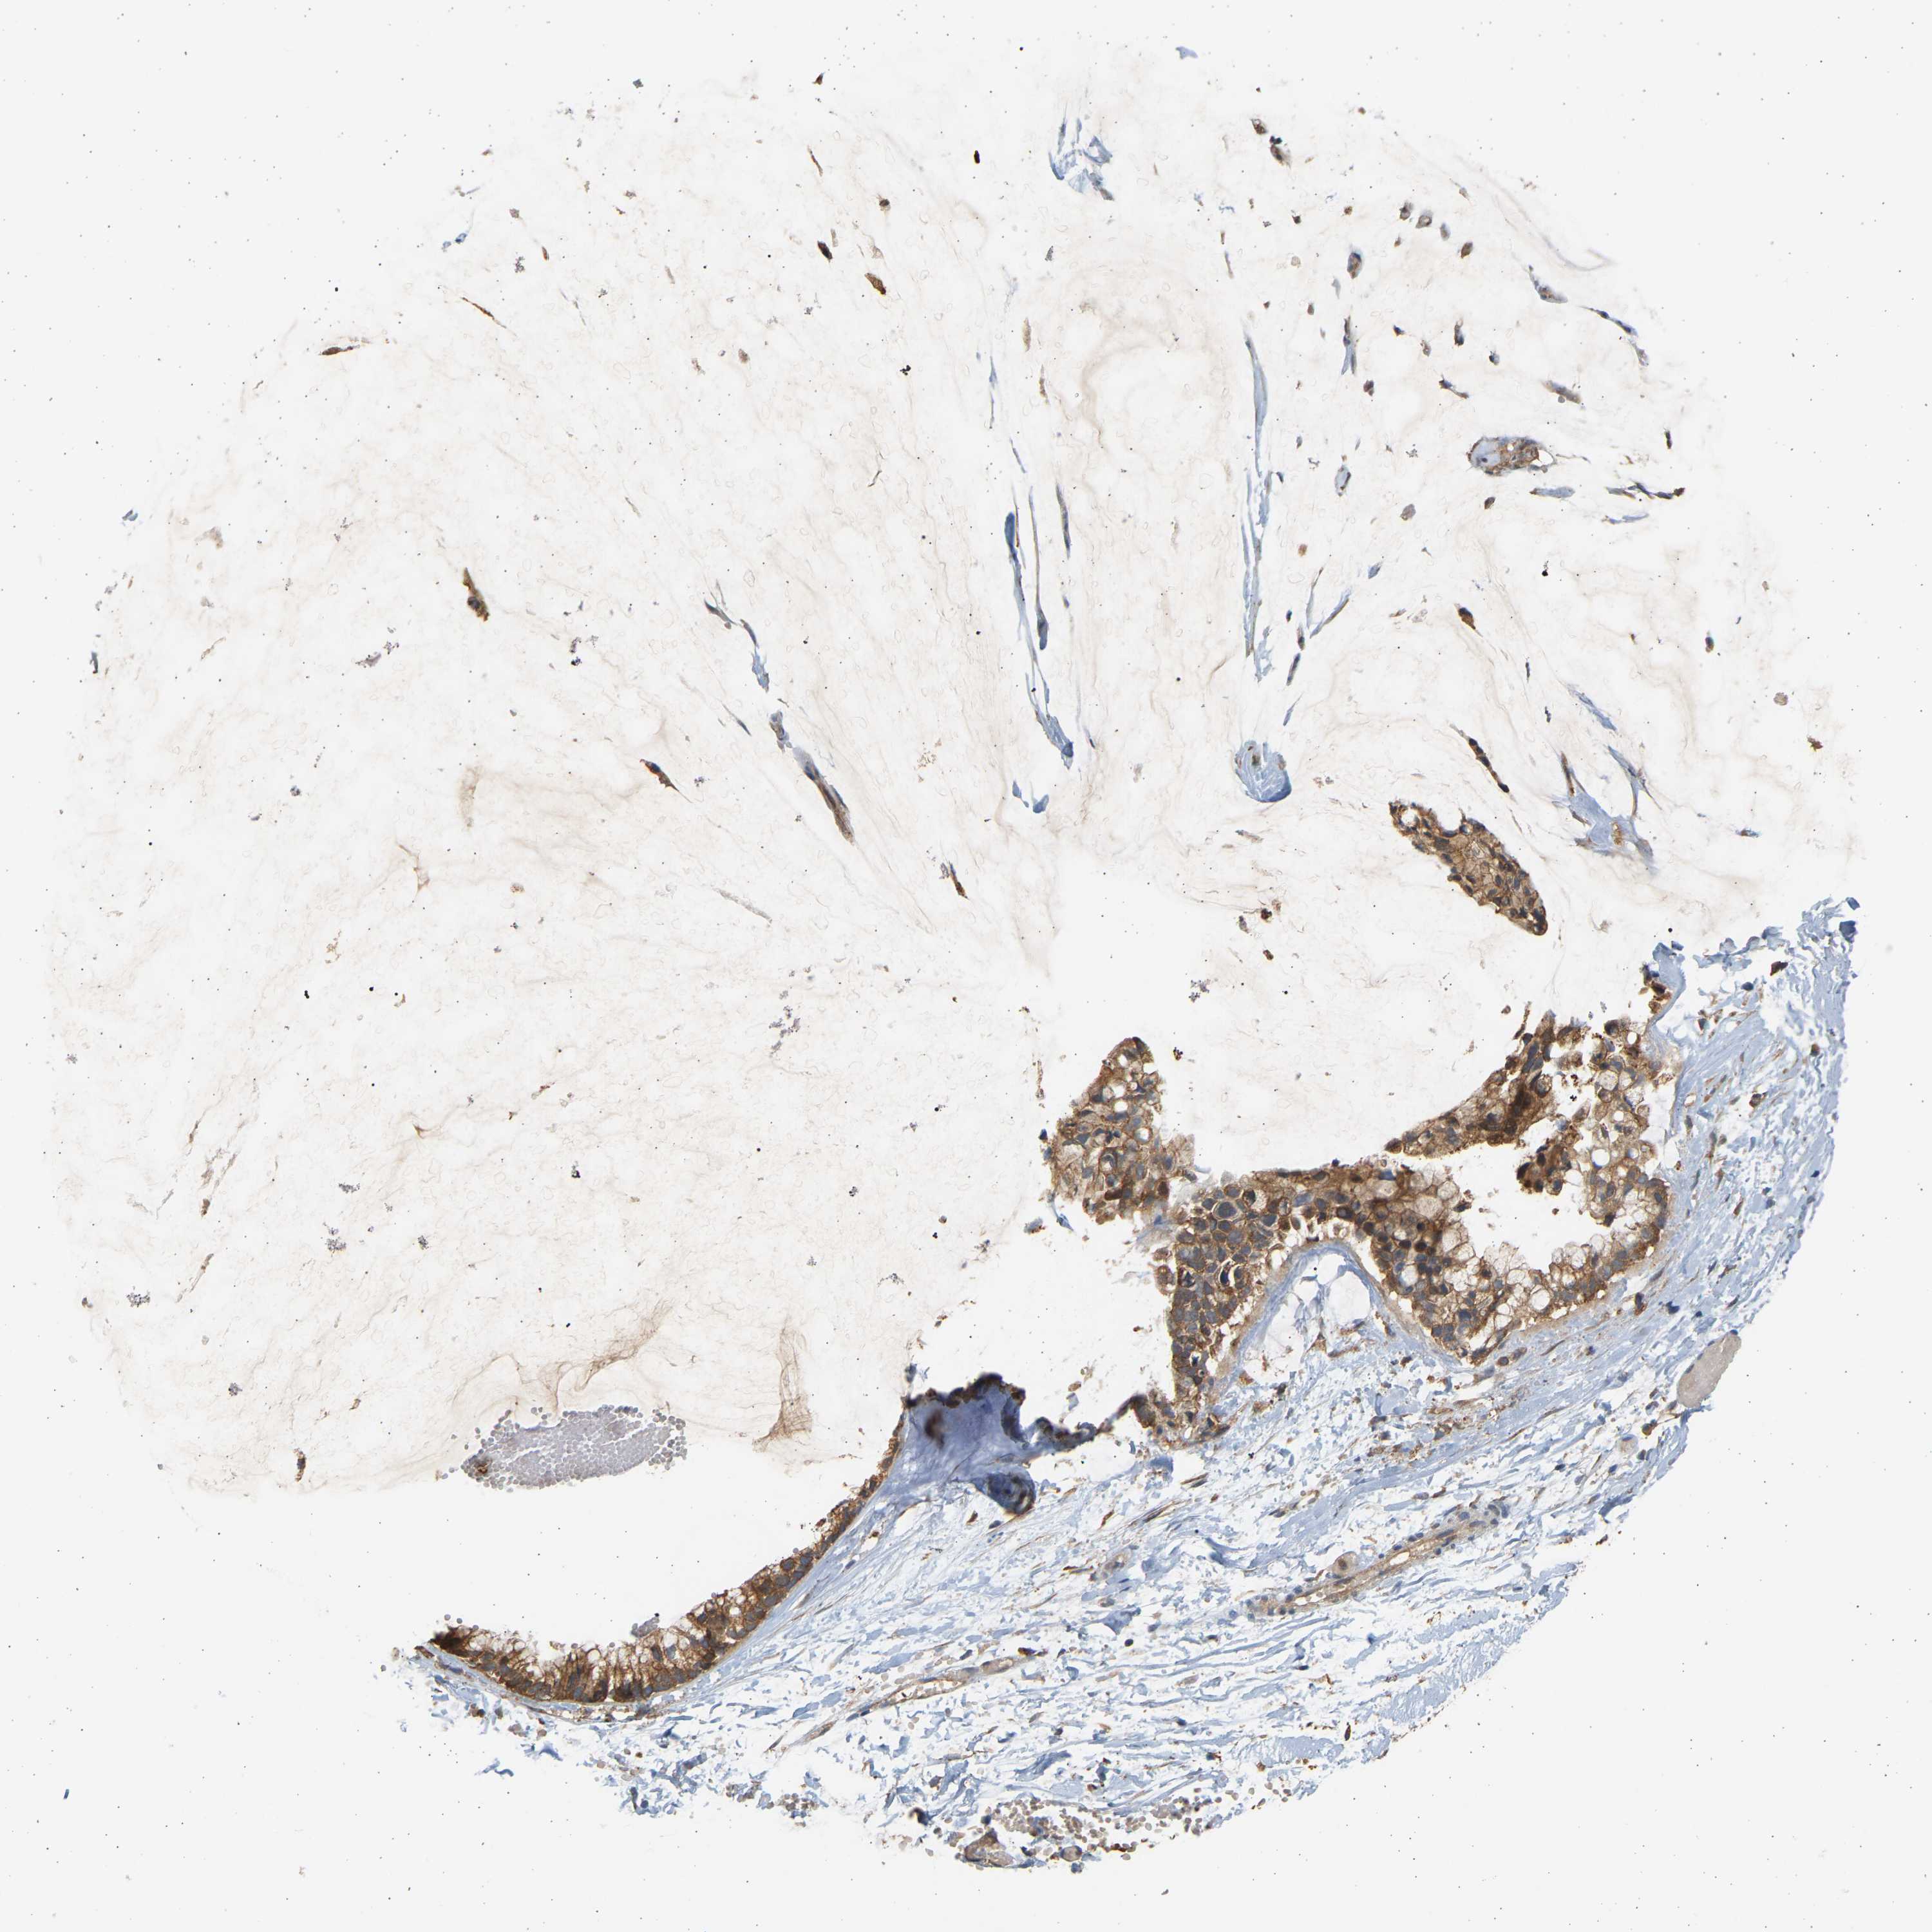

OVARIAN CANCER - Protein expressioni

A mouse-over function shows sample information and annotation data. Click on an image to view it in a full screen mode. Samples can be filtered based on level of antibody staining by selecting one or several of the following categories: high, medium, low and not detected. The assay and annotation is described here.

Note that samples used for immunohistochemistry by the Human Protein Atlas do not correspond to samples in the TCGA dataset.

Antibody stainingi

Antibody staining in the annotated cell types in the current human tissue is reported as not detected, low, medium, or high, based on conventional immunohistochemistry profiling in selected tissues. This score is based on the combination of the staining intensity and fraction of stained cells.

Each image is clickable and will lead to virtual microscopy that enables deeper exploration of all samples and also displays staining intensity scores, fraction scores and subcellular localization as well as patient and tissue information for each sample.

Antibody HPA058284

Antibody CAB020701

Staining

High

Medium

Low

Not detected

Intensity

Strong

Moderate

Weak

Negative

Quantity

>75%

75%-25%

<25%

None

Location

Nuclear

Cytoplasmic/membranous

Cytoplasmic/membranous,nuclear

Cystadenocarcinoma, serous, NOS

Cystadenocarcinoma, mucinous, NOS

Carcinoma, endometroid